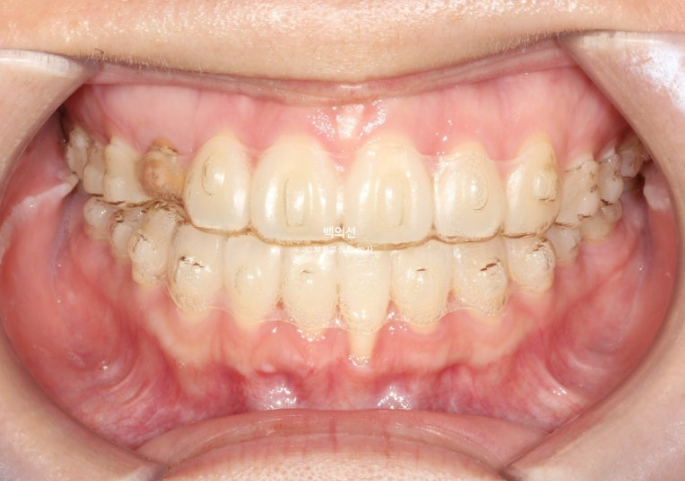

작년 가을 교정치료를 위해 내원한 환자분입니다.

오래 전 교정치료를 이미 받은 상태로 철사유지장치가 붙어있는 상태에서 오셨습니다.

아래 앞니 하나가 뿌리가 바깥으로 나가면서 잇몸퇴축이 심합니다.

잔존유치는 영구치 송곳니가 매복되는 바람에 남아있는 상태입니다.

잔존유치의 뿌리가 썩 튼튼하지는 않으나, 동요도는 전혀 없어 쓸때까지 쓰기로 합니다.

그런데 잔존유치에 교정력을 가할경우, 안그래도 약한 유치 뿌리가 녹을 수 있어서 잔존유치는 치료기간 내내 치아이동 없이 위치 잠금으로 계획해야 하고 어태치먼트조차 붙이지 않는 게 좋습니다.

색이 어두운 치아는 잔존유치에 레진을 덮어놓은 상태이고 이번기회에 재교정을 하면서 이 치아도 변색된 레진을 제거하고 라미네이트든 크라운이든 깔끔하게 치료를 원하셨습니다.